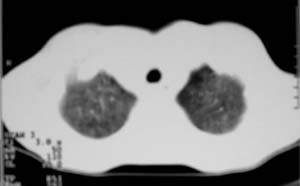

以下是引用zjzjr在2007-9-20 12:29:00的发言:[br]双肺磨玻璃改变,考虑肺水肿.

以下是引用yangzongshan在2007-9-20 18:29:00的发言:[br]两肺毛玻璃样改变,其内可见肺纹理影,无胸腔积液,故考虑肺泡蛋白沉积症

以下是引用276894491在2007-9-20 13:40:00的发言:[br]考虑肺水肿;外源性过敏性肺炎不排除。

以下是引用逸风在2007-9-20 20:45:00的发言:[br]两肺磨玻璃样改变,临床病史短,发热,考虑病毒感染合并右肺代偿性肺气肿.待排肺水肿,病史短,不支持肺泡蛋白沉着症.